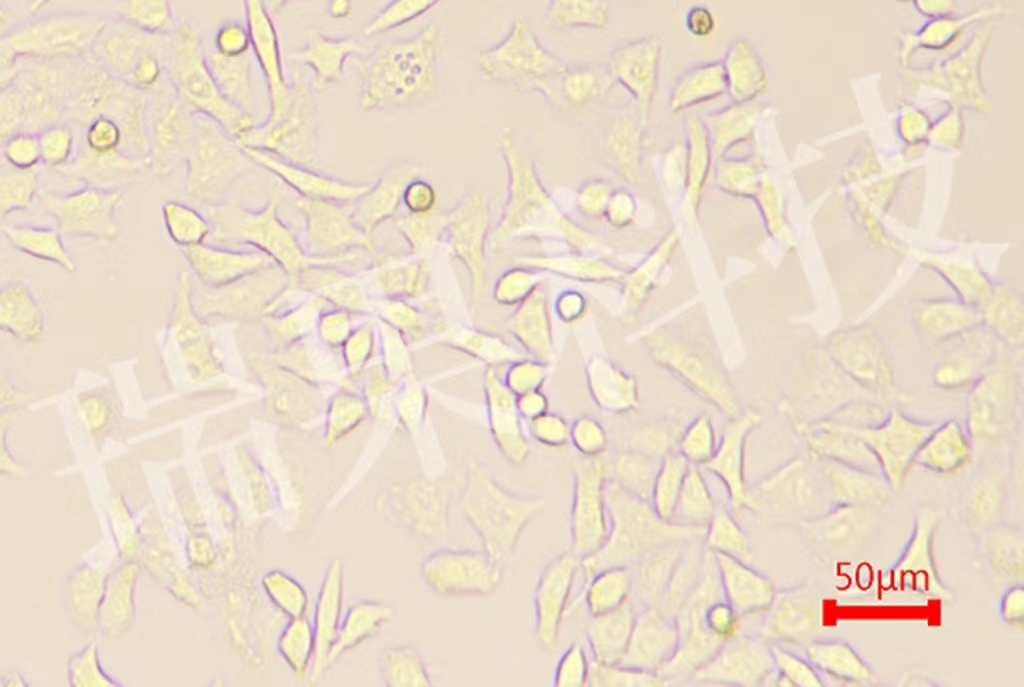

酵母菌镜检

酵母菌镜检 当前位置:首页 > 公司产品 > 产品服务 > 瑞果产品展示 > 细菌